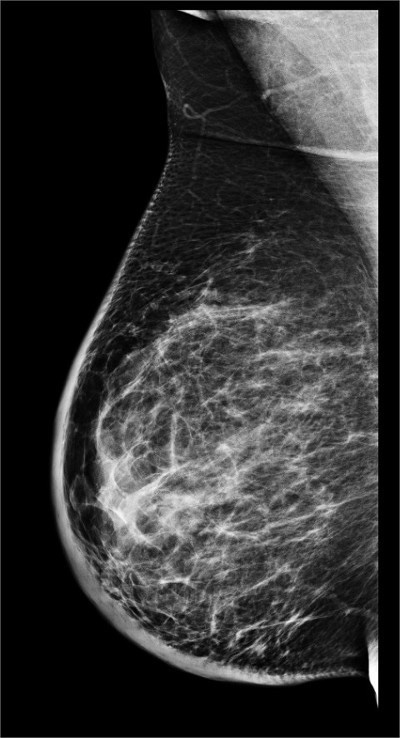

👉The mammogram shows trabecular thickening and an increased thickness of the skin.

👉Trabecular thickening is an increased prominence of linear structures in the breast, primarily corresponding to Cooper’s ligaments.

👉It is almost always seen in conjunction with skin thickening and indicates significant breast edema.

👉It has a number of different causes, including congestive heart failure, renal failure, venous or lymphatic obstruction, diffusely infiltrating carcinoma, and radiation.

👉When the cause is lymphatic obstruction, the obstruction can be the result of surgery, radiation, or lymphatic invasion by cancer.

👉Unilateral breast edema with increased trabecular and skin thickening sometimes occurs with congestive heart failure.

👉The pedal edema that develops during the daytime decreases at night and the fluid accumulates in the dependent breast in patients who sleep on their side.